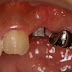

数年前に装着した部分冠(オールセラミックインレー)が脱離したとの事。

オールセラミックインレーにしては形成が薄いため、もう少し深く削らなければならないがあまり同意は得られず。

当時もあまり削らないでと前医と相談し浅く形成してSETしたとの事でした。

しかし、このままではまた同じ道を辿る可能性が非常に高いです。